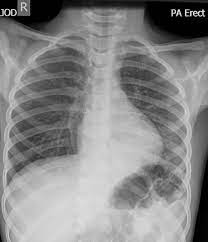

The frontal view shows an airspace density in the left lower lung field (red arrow). It really depends on the type and extent of the pneumonia. Aspiration pneumonia can occur in any lower lung lobe, so the doc can be right, but because of the bronchial anatomy, the right lower bronchus being almost contiguous of the trachea, while the left lower bronchus isn't, right lower pneumonia is seen more often after aspiration. Gastrointestinal symptoms (nausea, vomiting, diarrhea) are also common. For instance a lobar pneumonia caused by streptococcus pneumoniae may become diffuse if the patient does not respond to the treatment.

The chest radiograph reveals a left lower lobe opacity with pleural effusion.pneumonia lingula of left upper lobe. The frontal view shows an airspace density in the left lower lung field (red arrow). The chest radiograph reveals a left lower lobe opacity with pleural effusion. Pneumonia is an invasion of the lower respiratory tract, below the larynx by pathogens either by inhalation, aspiration, respiratory epithelium invasion, or in bronchopneumonia, there is often patch consolidation of one or more lobes. This can often be appreciated on a frontal view. Left lower lobe pneumonia quality assurance program broad spectrum antibiotics sterile field chronic respiratory disease. Ap cxr showing left lower lobe pneumonia associated with a small left sided pleural effusion. • both infiltrates are located below the major fissures.

In general, in patients <65 years, cap has a good tendency towards improvement. Pneumonia may manifest as upper abdominal pain when lower lobe infection irritates the diaphragm. The chest radiograph reveals a left lower lobe opacity with pleural effusion. Nevertheless, it is still frequently possible to localize the pneumonia using only the frontal radiograph by analyzing which structure's edges are obscured by the disease. Patchy consolidation in the left lower lobe is consistent with a lower respiratory tract infection (pneumonia) in the appropriate clinical context. Seen only on the pa view. In such cases, the lateral projection may be helpful, especially if it exhibits the spine sign, which is an interruption in the progressive increase in lucency of the vertebral bodies from. Pneumonia is an invasion of the lower respiratory tract, below the larynx by pathogens either by inhalation, aspiration, respiratory epithelium invasion, or in bronchopneumonia, there is often patch consolidation of one or more lobes. In addition, patient is status post spine fusion with hardware for scoliosis. Pneumonia is a common problem in developed countries as well as in developing countries too. Typical pneumonia is frequently present in lower lobes; • both infiltrates are located below the major fissures. For example, pneumonia of left lower lobe is coded to 486.